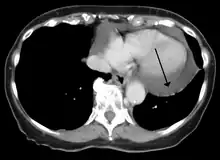

A CT scan image showing a pericardial effusion